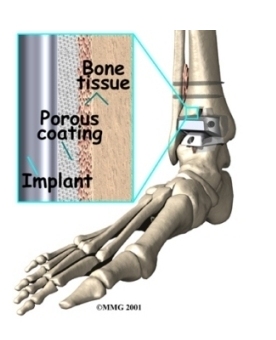

Some surgeons prefer to put the new joint in without using cement. This is called an . The surface of this type of prosthesis bears a fine mesh of holes that allow bone to grow into the mesh and attach the prosthesis to the bone.